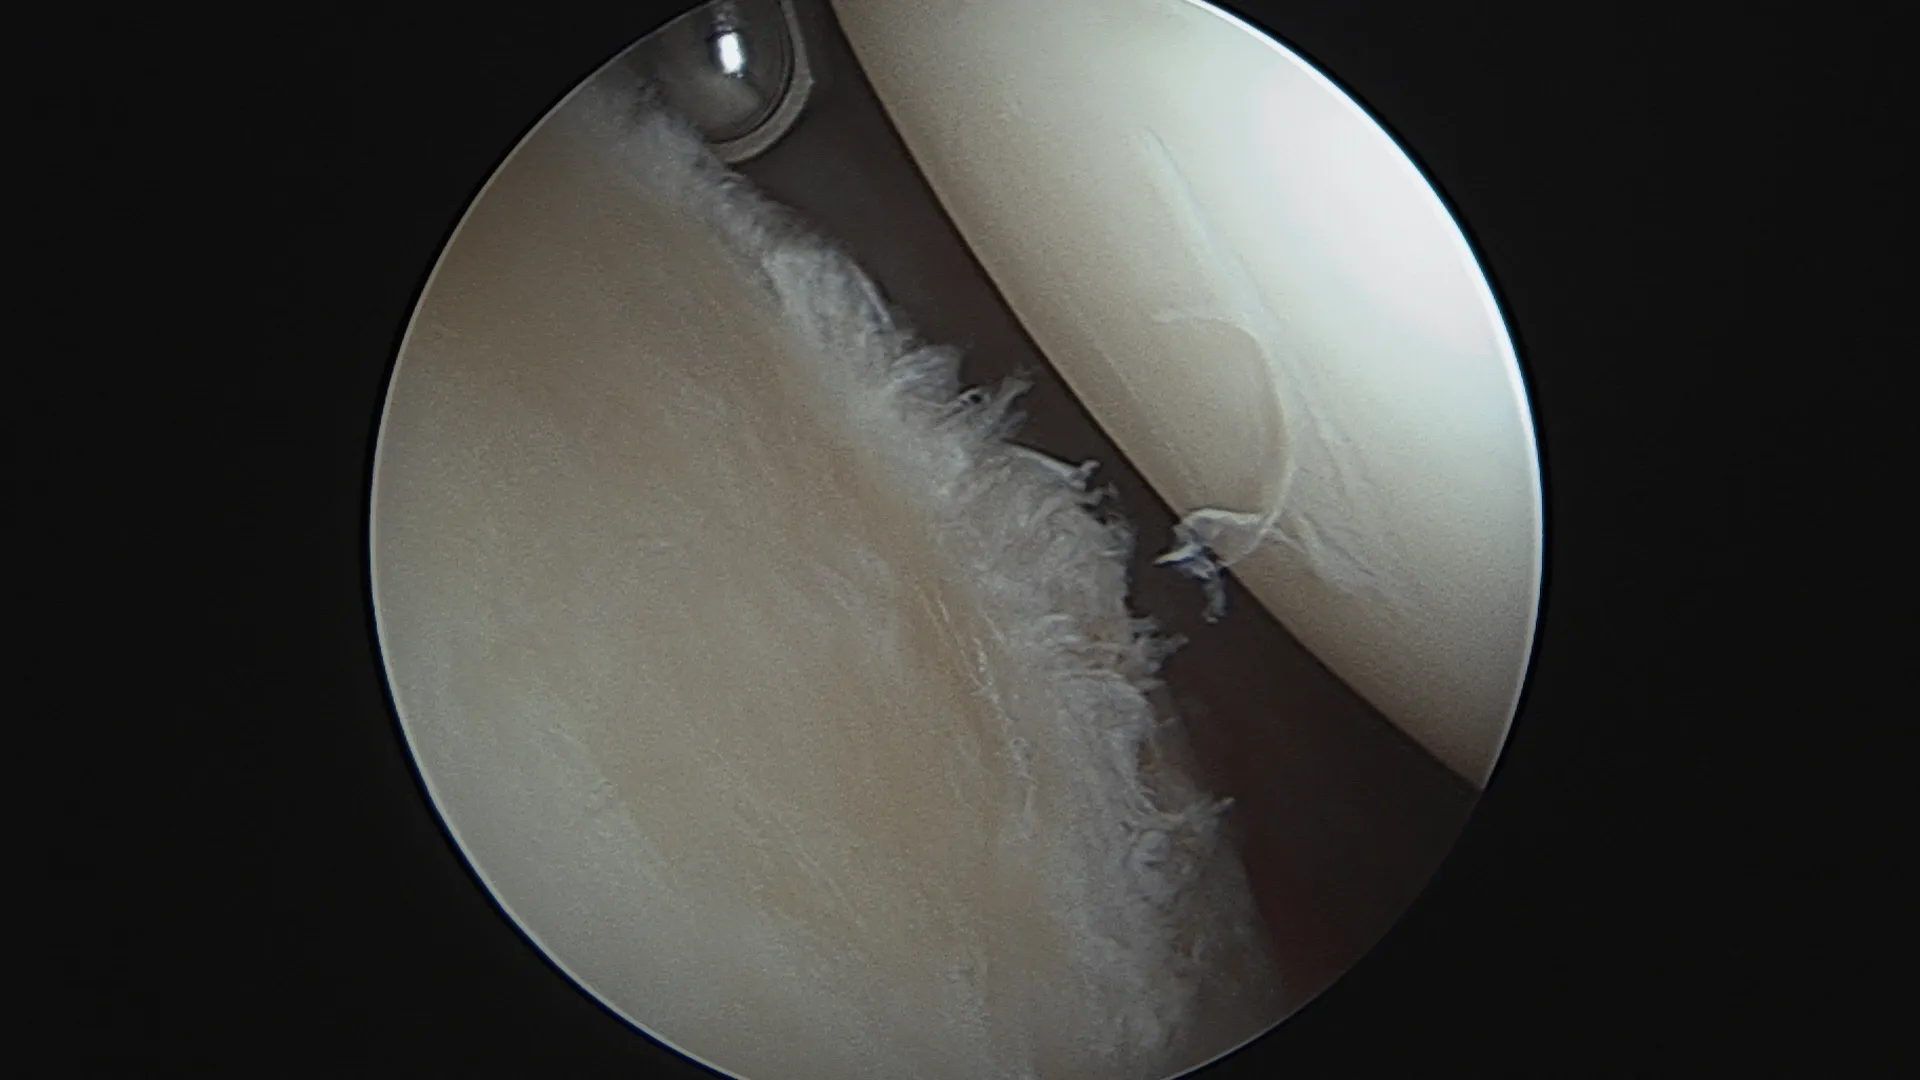

La lésion de Bankart

Le labrum se détache de la surface osseuse glénoïdienne. C'est la lésion la plus fréquente. Elle peut cicatriser spontanément — surtout après un premier épisode chez un patient jeune bien immobilisé. En cas de récidive, cette cicatrisation devient improbable.

Réparation de Bankart — sous arthroscopie

Pour qui ? Instabilité antérieure sans perte osseuse glénoïdienne significative (score ISIS ≤ 3).

Comment ? L'intervention est réalisée entièrement sous arthroscopie (vidéochirurgie), par 2 à 3 incisions de quelques millimètres seulement. Le labrum arraché est réinséré sur la glène à l'aide d'ancres résorbables sur lesquelles sont fixés des fils très résistants. Les ligaments gléno-huméraux distendus sont retendus dans le même temps opératoire.

Résultat : taux de succès élevé dans les indications bien posées. Reprise sport sans contact vers 4 mois. Non indiqué en première intention pour les sports de contact ou d'armé-contré.